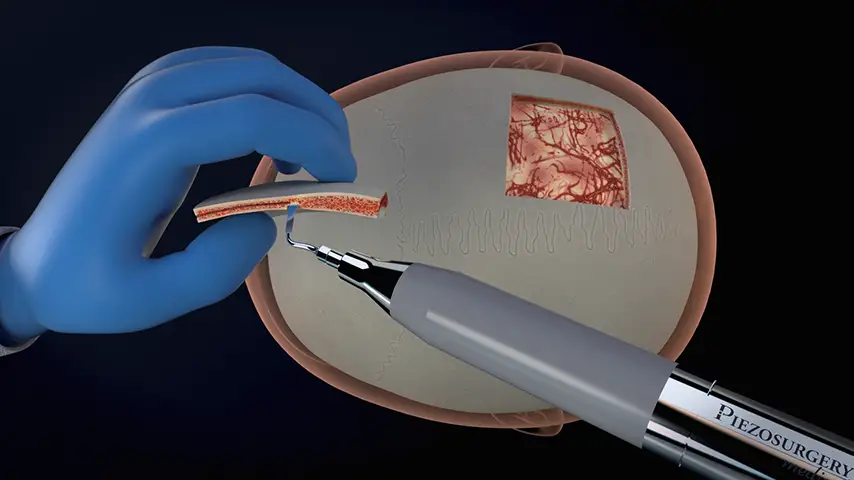

Craniotomy

and craniectomy

Reduced risk of CSF leak, better aesthetic result for the patient, sparing of fixation materials, dural and bone substitutes, due to selective and precise cutting.

Reduced heat ensures improved ossification with implants.